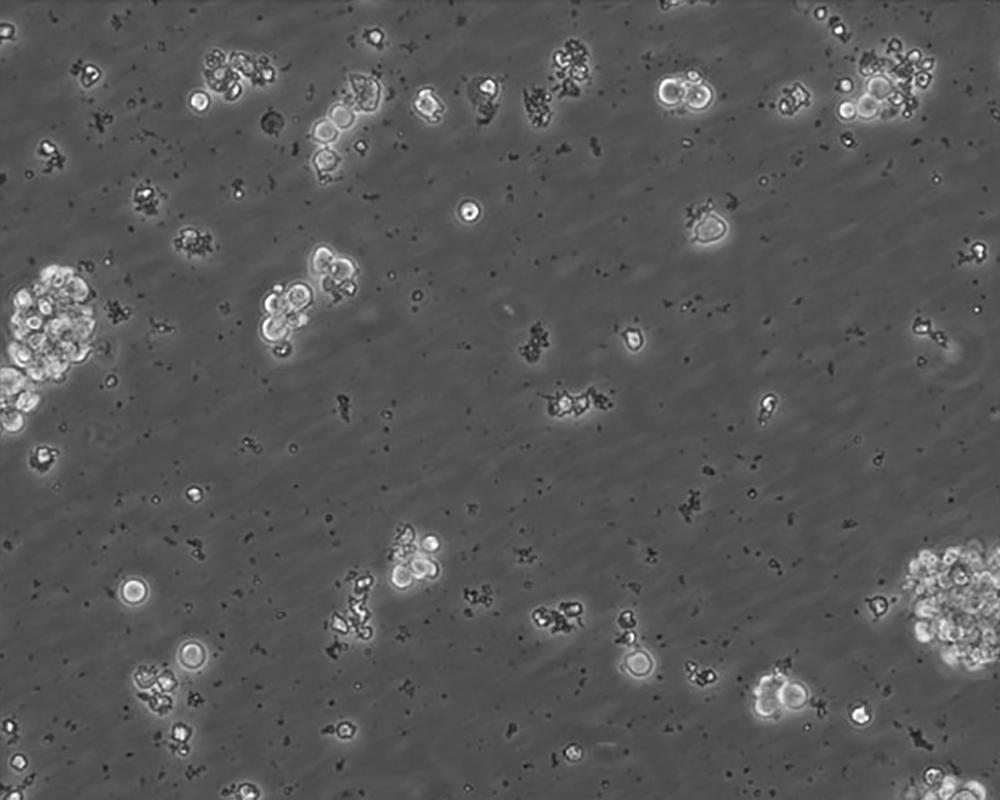

NK-92

中文名稱 人惡性非霍奇金淋巴瘤患者的自然殺傷細胞

生長特性 lymphoblast

形態特征 suspension, multicell aggregates

細胞描述 該細胞源于一位50歲的白種男人,可用作轉染宿主。該細胞對廣泛的惡性細胞有細胞毒性